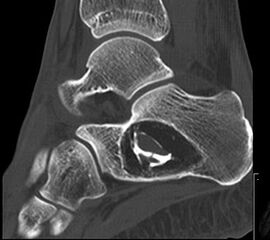

Die Computertomographie (CT) wird seltener als die MRT herangezogen um eine spezi­fischen Artdiagnose zu finden, liefert aber wertvolle Informationen zur Kortikalis­beschaffen­heit (Kontinuität, Stärke, enostale Arrosion) unterschiedlichster Knochenläsionen. Insbe­sondere die enostale Kortikalisarrosion, wie sie häufig bei chondrogenen Tumoren anzu­treffen ist, kann konkrete Hinweise liefern, die in Zusammenschau mit histologischen Befunden zu einer definitiven Diagnose führen (siehe Spezifische Entitäten: Enchondrom vs. atypischer chondrogener Tumor/Chondrosarkom). Die Computertomographie ist außerdem hilfreich in der Abgrenzung komplexer anatomischer Strukturen (z.B. 3D-Rekonstruktion) und sehr kleiner Knochenläsionen. Bei der Diagnose des Osteoidosteoms bleibt die CT Mittel der Wahl um die charakteristischen Veränderungen in der bildgebenden Diagnostik exakt darzustellen (Abb. 6). Die Gewebedichte von weichteiligen Tumoren, insbesondere von intra- und extraossären Lipomen, kann im Vergleich zum subkutanen Fettgewebe mithilfe der Houndsfield-Skala beurteilt werden.

Axiale CT-Aufnahmen eines Osteoidosteoms im Bereich des Calcaneus mit typischer Nidusbildung und perifokaler Sklerose (links). Bildgesteuerte Thermofrequenzablation der Läsion (rechts).